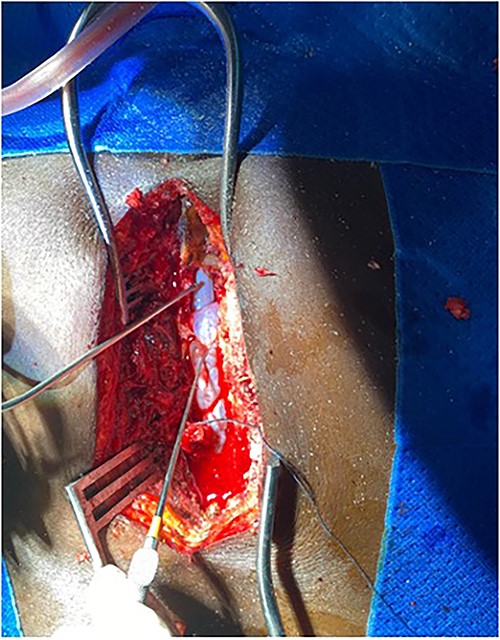

Surgery was recommended with the goal of cyst excision and spinal cord decompression, and the patient gave consent for surgery under general anesthesia. She was positioned prone on an operating table, and the surgery site was prepared in a standard sterile fashion after X-ray localization. A midline incision was made to expose the surgical levels of interest. T4–7 limited laminectomies were performed, with special care taken not to violate the facet joints on both sides. Laminectomy revealed a cystic lesion lying dorsal and to the right side of the spinal cord with a fistulous connection below theT6 exiting nerve root (Figs 3 and 4). Having carefully dissected the mass off the spinal cord, the fistulous connection was then isolated, and ligated as close to the lateral edge of the dura as possible and was subsequently disconnected from the dura (Fig. 5). The surgical bed was inspected and was copiously irrigated with warm saline and the wound was closed in layers. There were no intraoperative complications.

Fistulous connection of the cyst with spinal cord subarachnoid space.